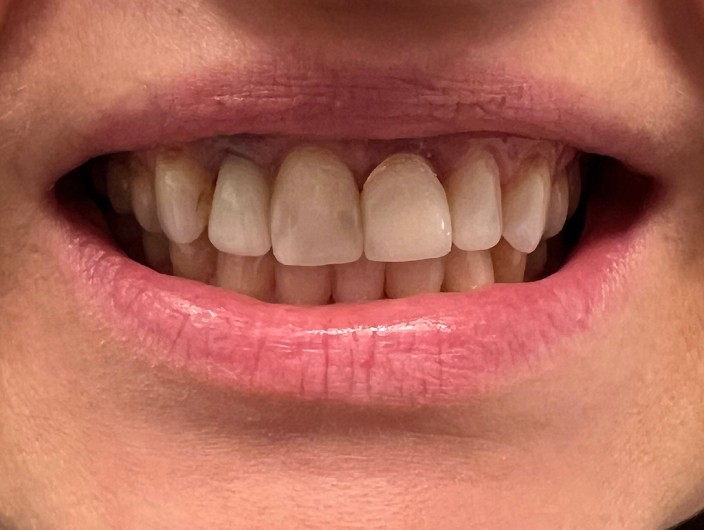

Zaprezentujemy serię poruszających historii pacjentów, którzy zdecydowali się na kompleksowe leczenie dentystyczne. Od przypadków zaawansowanej próchnicy, przez wypadki, które wymagały rekonstrukcji zębów, po pacjentów marzących o hollywoodzkim uśmiechu dzięki zastosowaniu licówek – każda historia jest dowodem na to, jak nowoczesna stomatologia może odmienić życie.

Poprawa estetyki uśmiechu: wybielanie zębów.